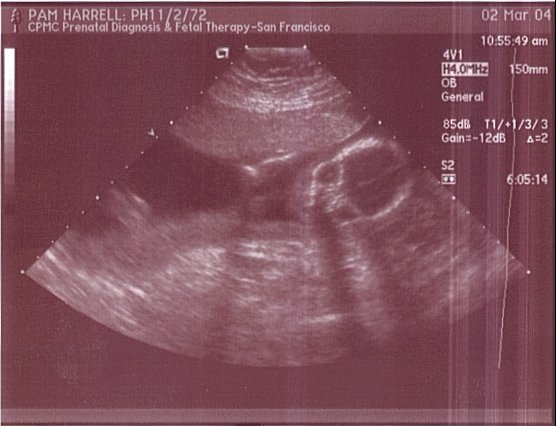

Here is a frontal face shot. Eye sockets and nasal structure are visible. Yes we have a little skeleton :-P. This was taken on March 2, 2004.